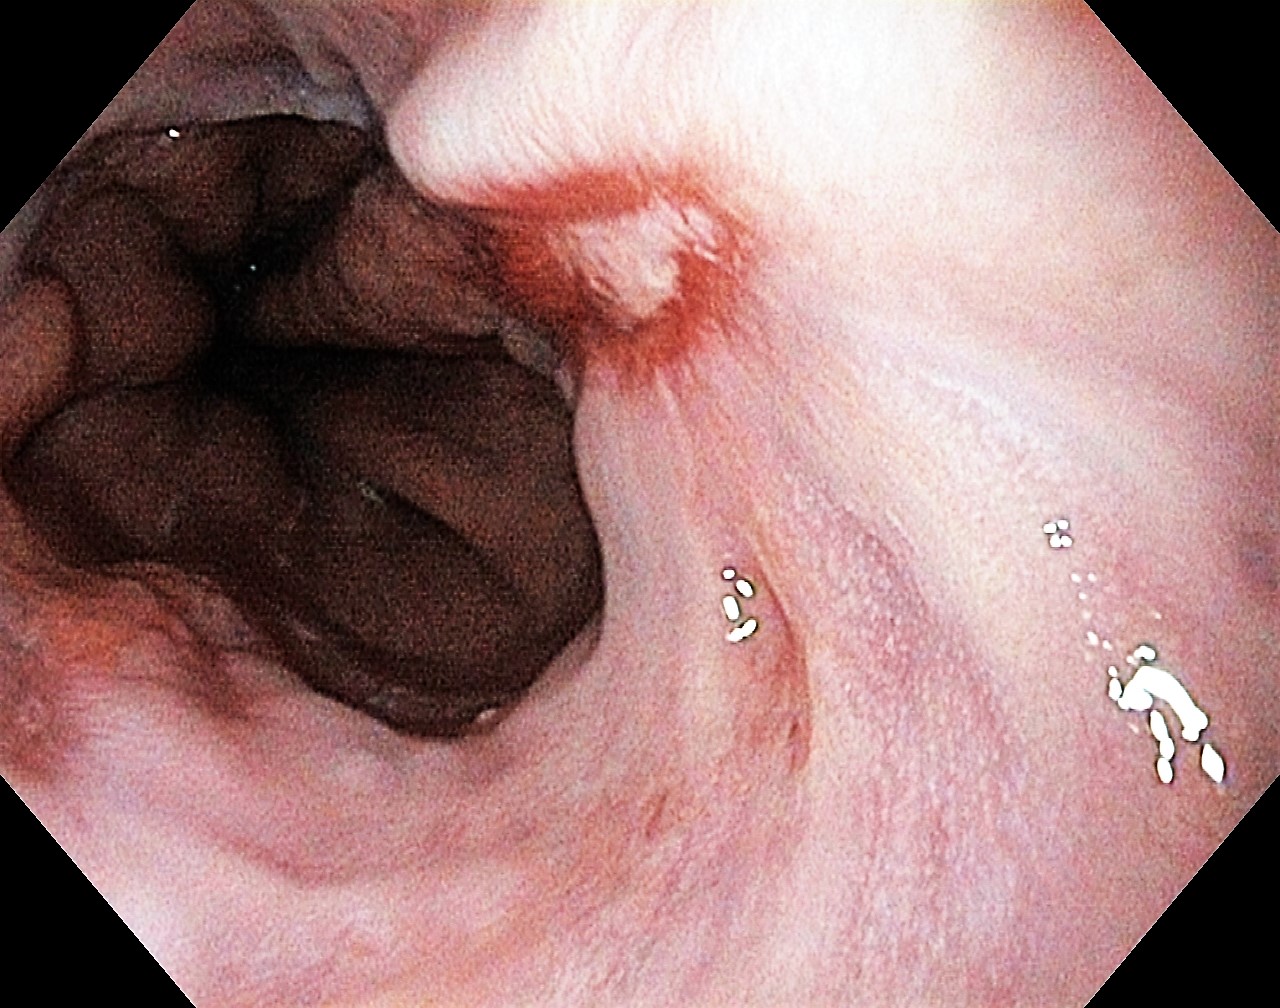

Reflux oesophagitis grade D according to the Los Angeles classification